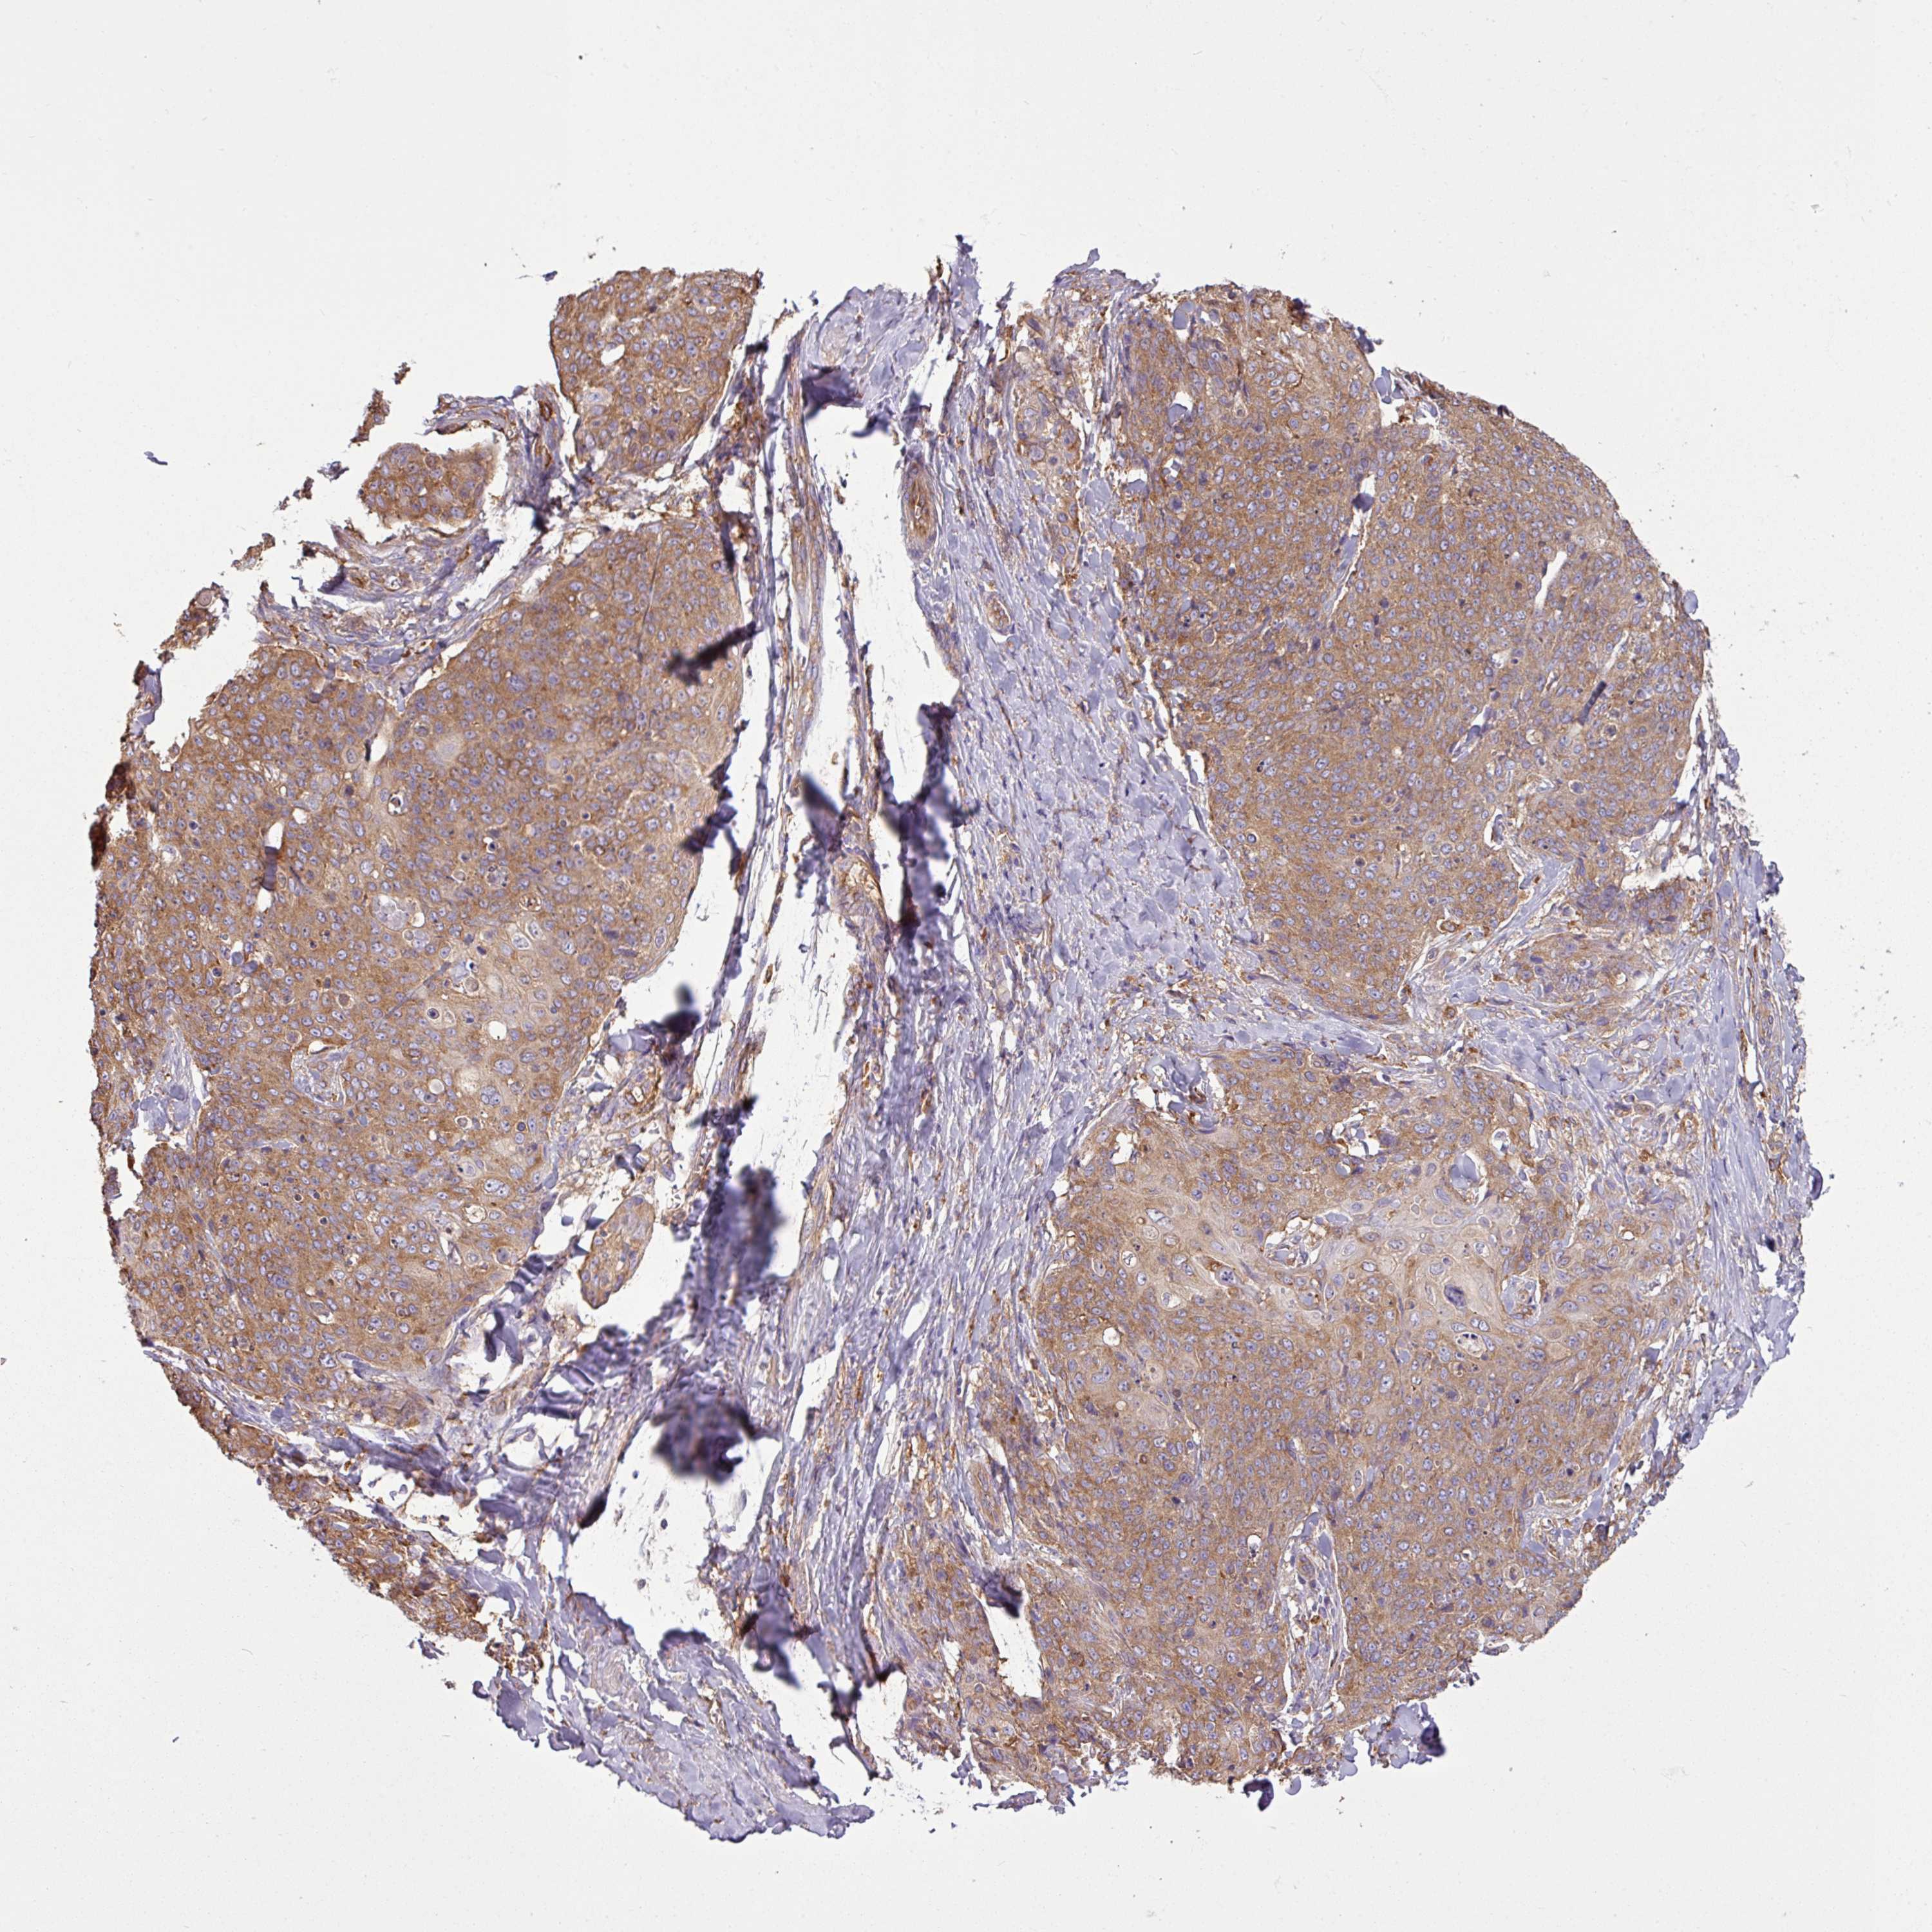

Basal cell and squamous cell cancer

SKIN CANCER - Protein expressioni

A mouse-over function shows sample information and annotation data. Click on an image to view it in a full screen mode. Samples can be filtered based on level of antibody staining by selecting one or several of the following categories: high, medium, low and not detected. The assay and annotation is described here.

Antibody stainingi

Antibody staining in the annotated cell types in the current human tissue is reported as not detected, low, medium, or high, based on conventional immunohistochemistry profiling in selected tissues. This score is based on the combination of the staining intensity and fraction of stained cells.

Each image is clickable and will lead to virtual microscopy that enables deeper exploration of all samples and also displays staining intensity scores, fraction scores and subcellular localization as well as patient and tissue information for each sample.

Antibody HPA049854

Antibody HPA056520

Staining

High

Medium

Low

Not detected

Intensity

Strong

Moderate

Weak

Negative

Quantity

>75%

75%-25%

<25%

None

Location

Nuclear

Cytoplasmic/membranous

Cytoplasmic/membranous,nuclear

Basal cell carcinoma

Squamous cell carcinoma, NOS

Squamous cell carcinoma, metastatic, NOS